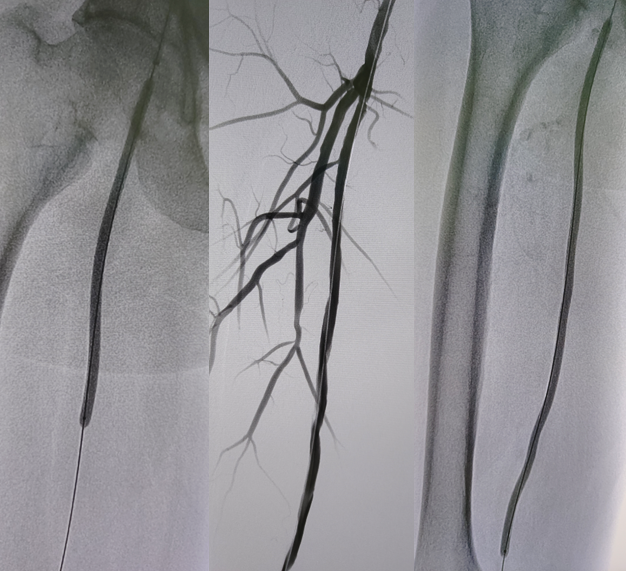

病例2(股腘动脉长段闭塞):

另一例长段闭塞病变,IVUS证实导丝真腔通过后,指导术者选择了合适尺寸的Rotarex导管进行减容,联合普通球囊(POBA)预扩及DCB治疗,获得了满意的管腔,避免了支架植入。

图:导丝通过后3mm球囊预扩

图:多处假腔通过,遂5mm球囊预扩

图:一期支架植入